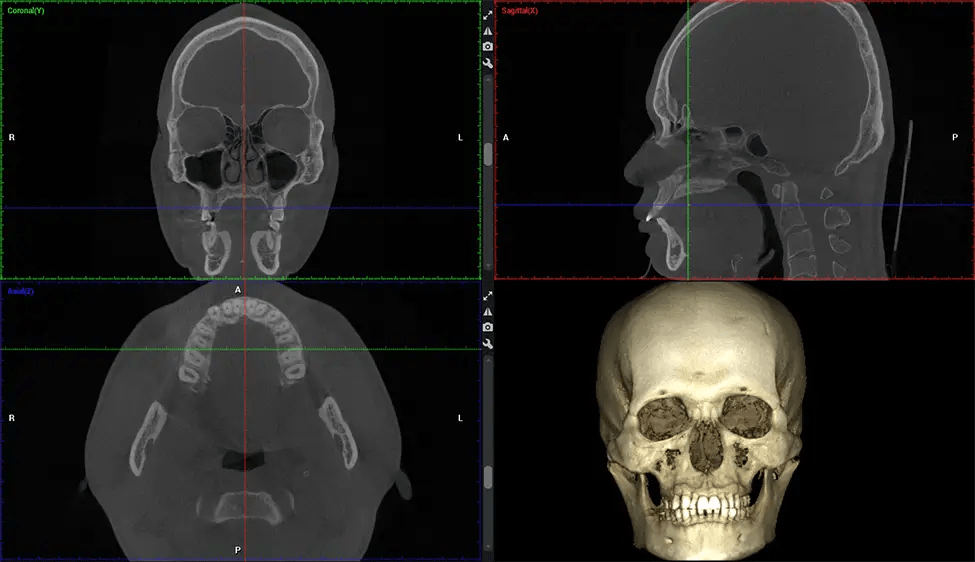

This 3D scan, called cone beam computed tomography, gives your dentist a more complete image of your oral anatomy and disease processes than a traditional X-ray. Unlike conventional X-rays, which capture a 2D image of your mouth from various angles, a 3D scan takes multiple digital X-rays for one image. It provides a complete view of your jaw, teeth, nerves, and soft tissues. This enhanced view allows dentists to detect minor issues not visible in traditional 2D scans, such as impacted wisdom teeth or bone fractures in the sinus cavity.

There are many benefits to using CBCT technology, especially compared to the traditional 2D X-ray format. One of the most significant advantages of CBCT scans is that they provide much more information than traditional X-rays. A scan lets your dentist see images from all angles of your jaw and mouth, including your sinuses, nasal cavity, cheekbones, and other surrounding areas. This added information helps your dentist craft a comprehensive treatment plan that addresses all aspects of your oral health.

Another significant benefit is that 3D imaging provides more precise images of your bone structure. These images are more detailed, providing you with a more accurate diagnosis. An accurate diagnosis means better treatment for you.

The patient is first positioned in the CBCT scanner, which typically consists of a rotating arm that houses the X-ray source and a detector. The patient’s head is immobilized to ensure accurate image capture. The X-ray source and detector rotate around the patient’s head, capturing various X-ray images from multiple angles. As the X-ray source rotates, it emits the cone-shaped X-ray beam towards the detector. The detector captures the X-ray images, which are then processed by the CBCT software.

After the scanning process, the captured X-ray images are processed by the CBCT software, which applies algorithms to reconstruct a detailed 3D image of the scanned area. The software compiles these individual X-ray images and creates a digital 3D representation of the patient’s anatomy. The reconstructed 3D CBCT image can be viewed and analyzed by the dentist or radiologist. This image can be manipulated, rotated, and zoomed in or out to examine specific structures and evaluate the patient’s condition.